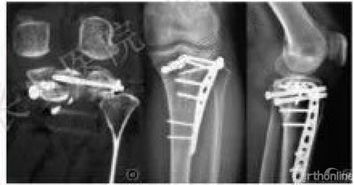

胫骨平台是位于胫骨上端的一个平台,与股骨的髁部形成膝关节。胫骨平台骨折是指胫骨平台部位发生的骨折,可能是由于直接撞击、跌倒或扭伤等原因引起。根据骨折的严重程度和位置,可分为多种类型,如单纯骨折、粉碎性骨折等。

胫骨平台骨折的保守治疗方法主要包括以下几种:

胫骨平台骨折的保守治疗通常需要4-6周的时间进行石膏固定,之后进行膝关节屈伸功能锻炼。一般而言,患者在2个月内可以恢复到正常活动,3个月左右可以完全恢复正常。具体恢复时间因个体差异而异。